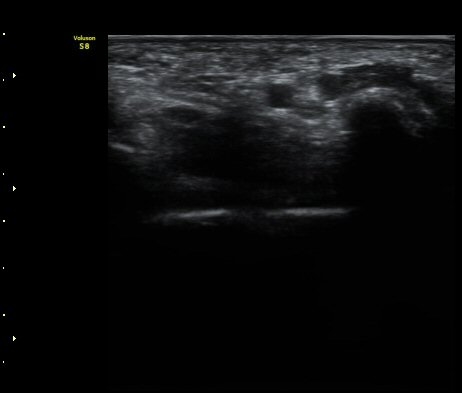

ÃÊÀ½ÆÄ °Ë»ç

¤º